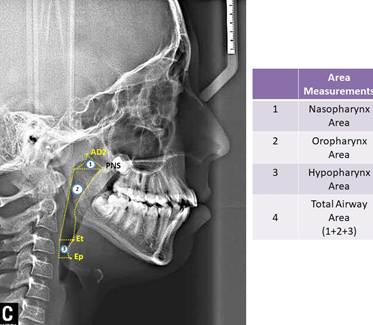

In study, 35 cephalometric points (Figure 1), 8 cephalometric planes, and 30 cephalometric measurements (Figure 2) were used. In the cephalometric analysis; 5 craniofacial, 8 nasopharyngeal, 7 oropharyngeal, 2 hypopharyngeal (Figure 3), 9 hyoid measurements (Figure 4) and 4 area measurements (Figure 5) were used.

Figure 3 Pharyngeal airway measurements used in study. (PPS: palatal pharyngeal distance: on the line passing from PNS, parallel to FH. SPSS, superior posterior pharyngeal distance: on the line passing from the midpoint of the soft palate, parallel to FH. MPS, middle pharyngeal distance: on the line passing from P, parallel to FH. IPS, inferior pharyngeal distance: on the line passing from cv2a, parallel to FH. EPS, epiglottic pharyngeal distance: on the line passing from E, parallel to FH.)